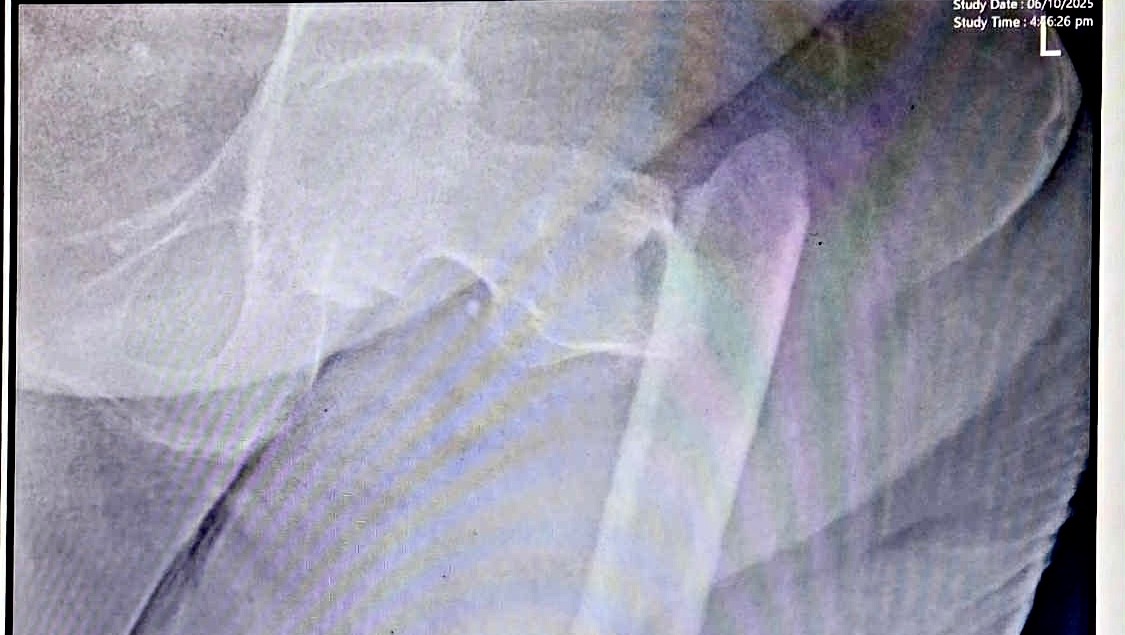

Back in October 6, 2025, Lola Susing had a ground-level fall at home. It all happened so fast. She was trying to get to the bathroom in the middle of the night, she got off balance despite the walker and fell. She cried out in pain, when my father and uncle heard her it was already too late. They rushed to help her — only to learn in the ER that she had fractured her left femur (thigh bone).

The doctors told us she needs surgery to repair the bone. It’s the best way for her to recover, relieve her pain, and regain even a bit of mobility. The estimated cost for the surgery, medications, and hospital stay is around ₱300,000.